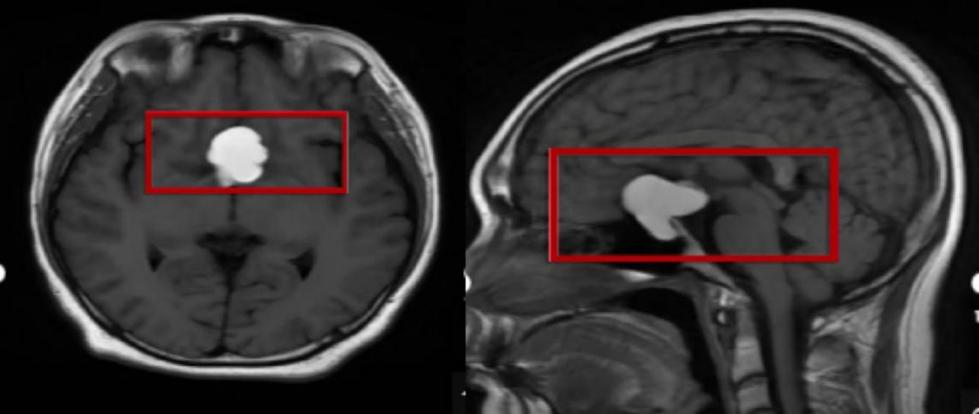

验光发现其左眼矫正视力仅0.5+,眼底排查仅见高度近视相关的豹纹状改变,无其他明显异常。经斜弱视与小儿眼科金丽文主任联合会诊,发现小伟左眼瞳孔偏大、对光反射迟钝,存在颞侧视野缺损。凭借多年从医经验,金丽文主任判断其视力下降并非单纯眼疾,建议立即完善颅脑MRI检查。结果显示,小伟头颅鞍区及鞍上有一约32.6mm×25.1mm×32.8mm的异常信号灶,视交叉受压。最终确认,颅内占位才是其视力下降、视野缺损的根源,随后小伟已在上海接受治疗。

小伟检查报告 通讯员供图

眼底病科孟冠军医生详细了解病情后,安排了全面视野检查,发现其双眼视野均存在异常。结合丰富的临床经验,孟冠军医生怀疑病因在颅内,立即建议进行头颅核磁共振检查。泉州爱尔眼科医院随即开通与泉州医高专附属人民医院的绿色通道,次日便为孙阿姨完成检查,然而检查结果让大家心头一紧,孙阿姨的颅内鞍区确实有一个囊性占位。

孙阿姨检查报告 通讯员供图